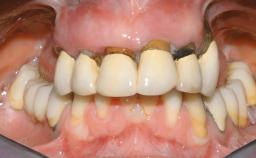

A 63-year-old male patient was referred for a consultation and treatment of partial edentulism in the maxilla. The patient presented with residual anterior teeth and declined a partial removable prosthesis. He reported that the maxillary posterior teeth had been extracted due to mobility and periodontal disease two months before the consultation. The patient’s chief complaint was that his residual maxillary teeth were mobile and that he was unable to chew. The patient’s desire was a stable and comfortable fixed maxillary rehabilitation. The patient was a light smoker (fewer than 10 cigarettes/ day), and his medical history was without significant findings. He was not on any regular medication at the time of consultation. The extraoral examination revealed a normal physiognomy with a correct distribution of the facial thirds. The patient presented a low lip line, and the transition line between teeth and soft tissues was not exposed during a forced smile.

Lip Line No exposure of papillae Exposure of papillae Full exposure of mucosa margin

Periodontal Phenotype Low-scalloped, thick Medium-scalloped, medium-thick High-scalloped, thin

Shape of Tooth Crowns Rectangular Triangular